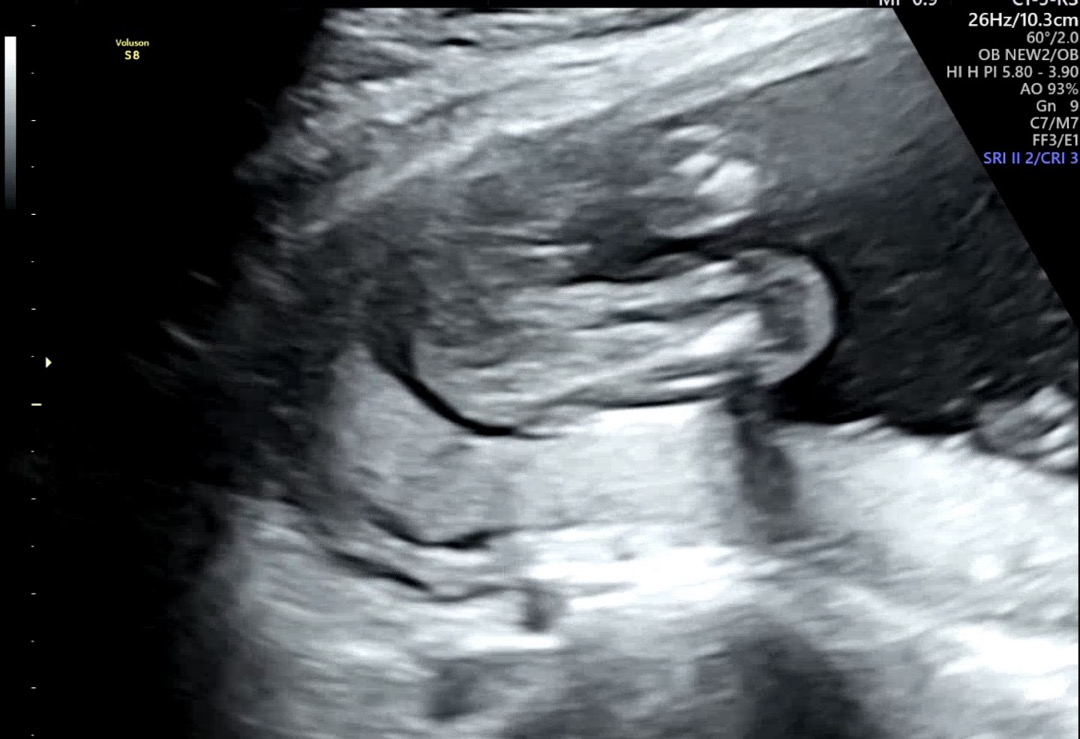

16주차 촘파 도와주세요ㅠㅠㅠㅠ

가운데 보이는것같다고 하시는데… 선배님을 눈엔 어떠세용ㅎㅎㅎ

아들인거같아요

아들이요!!

아들 한표요